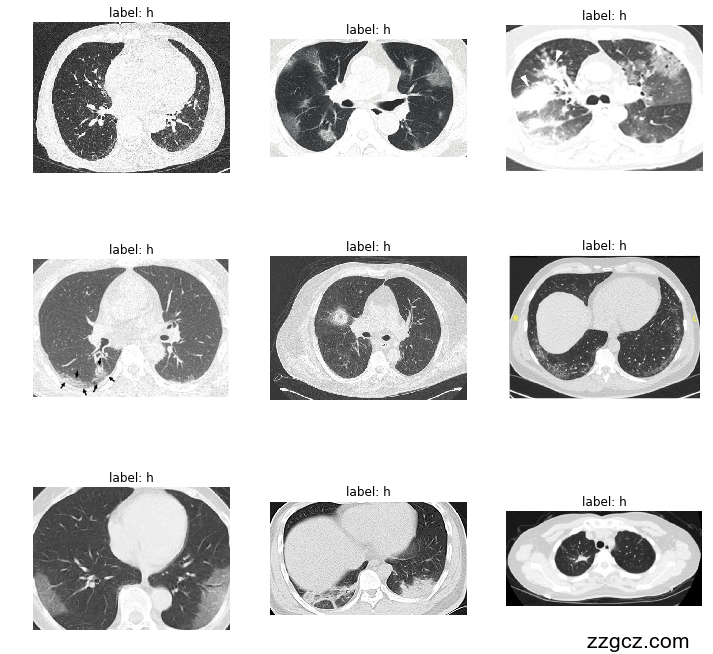

通过搜集新冠肺炎CT图片数据资料了解到中重症新冠肺炎患者的肺部可能会出现磨玻璃影,铺路石症等症状。该模型中引入了Deformable卷积(DeformConv2D),这是一种改进的卷积操作,用于提升卷积神经网络处理图像特征的灵活性。传统卷积操作使用固定的卷积核,而Deformable卷积通过学习空间上的偏移量来动态调整卷积核的采样位置,使得卷积操作可以适应更加复杂的形状和纹理变化。Deformable卷积特别适合处理包含非刚性结构或几何形变的对象,因此在一些医疗影像分析、自动驾驶视觉系统中表现出色。在该项目中,DeformConv2D的加入不仅增强了模型对特征的捕捉能力,还提高了在处理CT图像中不同区域间复杂边界和纹理变化的效果。

COVID-CT-2019冠状病毒疾病CT图像数据集包括349例CT图像,其中216例为COVID-19,其余的都为非新冠肺炎CT影像。

该项目使用的CT影像数据集包含了两类图像——“CT_COVID”和“CT_NonCOVID”,分别代表COVID-19阳性和阴性病例的CT扫描图像。这种数据集具有高分辨率、灰度变化明显、结构复杂等特点,特别适用于医疗影像分类任务,但也对模型的识别能力提出了较高的要求。为了提升模型的泛化性和稳健性,数据集在预处理中进行了精细的处理。